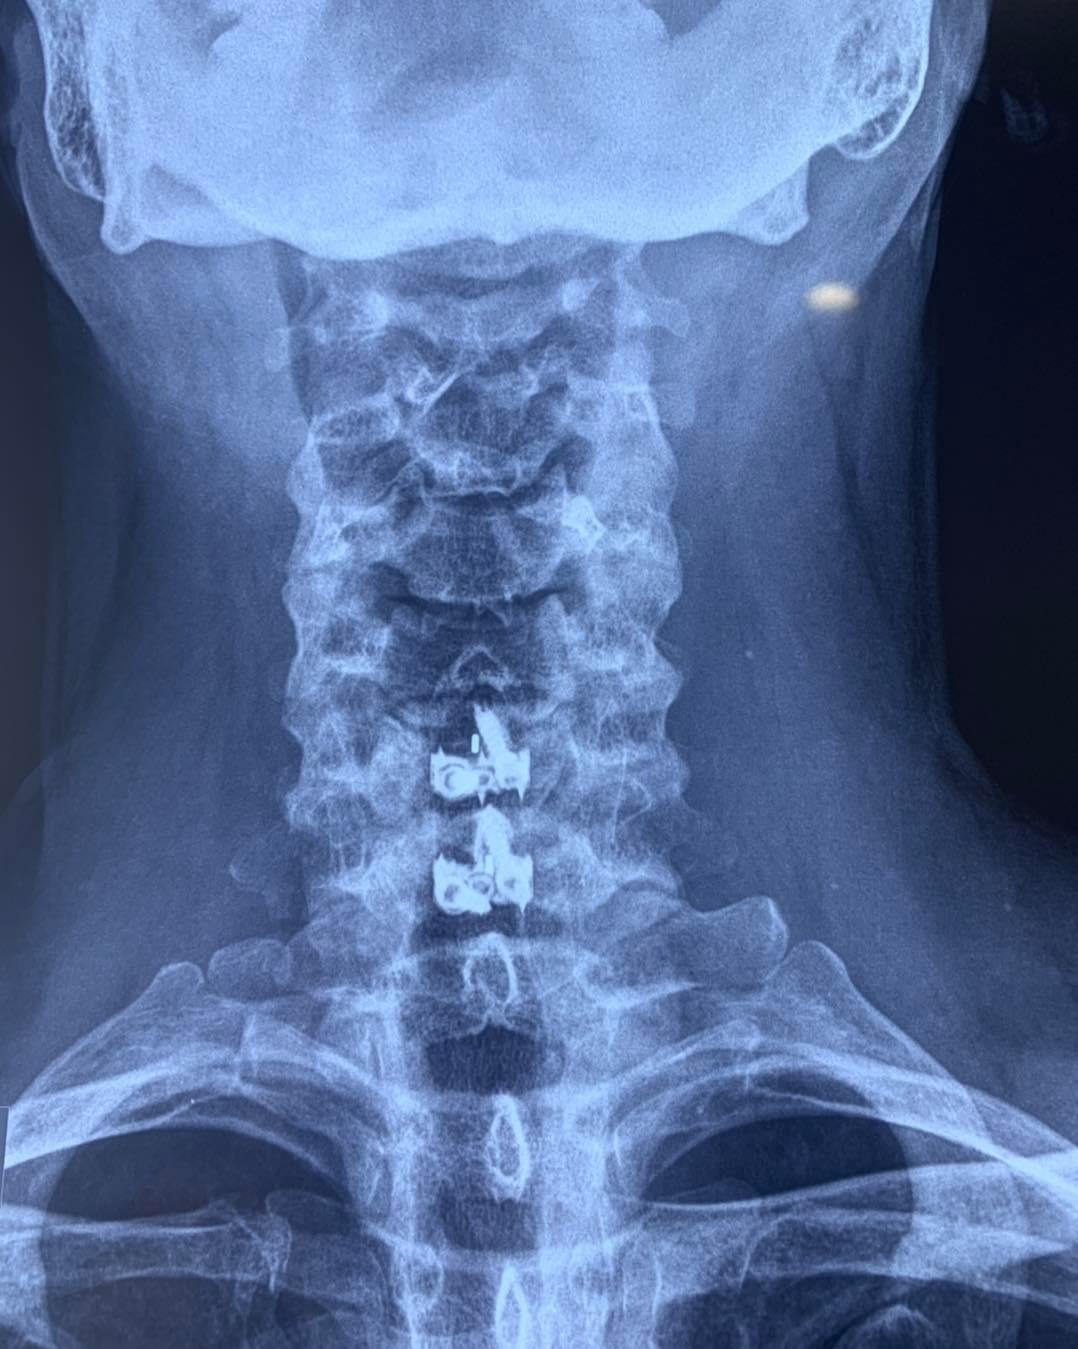

RESULTADOS